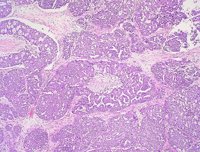

Aproximadamente, un 20 por ciento de las mujeres que tiene un cáncer de ovario del tipo seroso de alto grado tiene una mutación del tipo BRCA, en estos casos - al tratarse de una mutación genética con patrón familiar- hay que ser conscientes de que puede haber alguna portador en la familia y, por tanto, el médico recomienda que se haga un estudio genético para valorarlo.